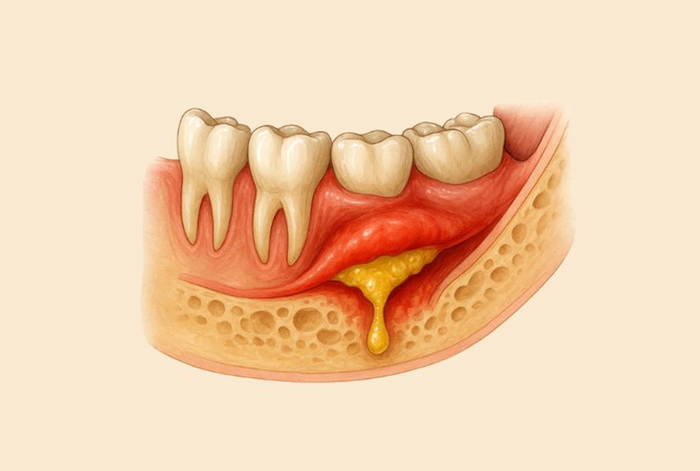

16 ) Лечение воспалительных заболеваний полости рта: вскрытие абсцесса поднадкостничного, мягких тканей в полости рта

Это наш любимый флюс. Подробнее тут:

Пожалуй, самая важная процедура в стоматологии, так как она позволяет предотвратить наиболее тяжелые осложнения в виде нагноения лица и шеи. Считаю, что её должен уметь делать каждый стоматолог, даже ортодонт. В случае апокалипсиса лишь она вместе с удалением зубов будет востребована у пациентов до появления первых ростков новой цивилизации.

Требуется всего 3 инструмента: скальпель, гладилка (ею вносят пломбу в зуб или отделяют десну от зуба при удалении) и маленькая полоска резины из медицинской перчатки.

Кстати, эта манипуляция делается абсолютно одинаково, что в амбулатории Мухосранска за полярным кругом, что в элитной клинике в центре Москвы.